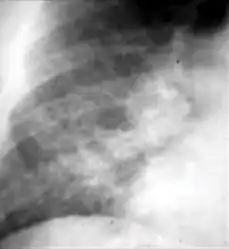

3. Nodule with poorly defined margins - Round density within the lung parenchyma, also called a tuberculoma. Nodules included in this category are those with margins that are indistinct or poorly defined (tree-in-bud sign[3]). The surrounding haziness can be either subtle or readily apparent and suggests coexisting airspace consolidation.

-

Chest x-ray showing nodule with margins that are indistinct or poorly defined (tree-in-bud sign) in post-primary pulmonary TB.